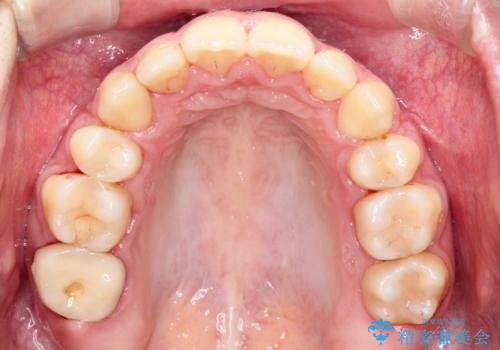

【ハーフリンガル】口元を下げたい!

- 口元が出ていることを主訴に来院されました。

歯を抜いてスペースを作ることで、前歯を下げることができました。

ハーフリンガルということで治療期間が3年近くかかりましたが、口元もしっかり下がり満足していただきました。